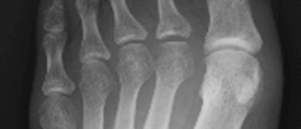

X線検査では、RAが進行すると関節周囲の骨粗鬆症に加えて、関節裂隙の狭小化、骨びらん、強直などがみられます。しかし、RA発症の初期(図1、図3)ではこうしたX線の変化はほとんどみられません。関節エコー検査(図2)やMRI検査(図4)を用いるとX線検査では認めることのできないRAの早期の変化である活動性滑膜炎や骨びらんを確認することができるので、RAの早期診断と早期治療につながります。